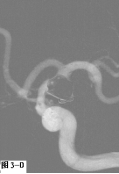

图3 采用支架辅助双微导管技术栓塞左侧颈内动脉后交通段不规则形态动脉瘤。A.DSA显示囊性动脉瘤破裂后在瘤体顶端又形成一假性动脉瘤;B.工作角度发现该动脉瘤瘤颈宽,颈内动脉直接成为瘤颈一部分;C.在部分释放支架情况下,交替填塞微弹簧圈;D.动脉瘤填塞致密,载瘤动脉通畅。